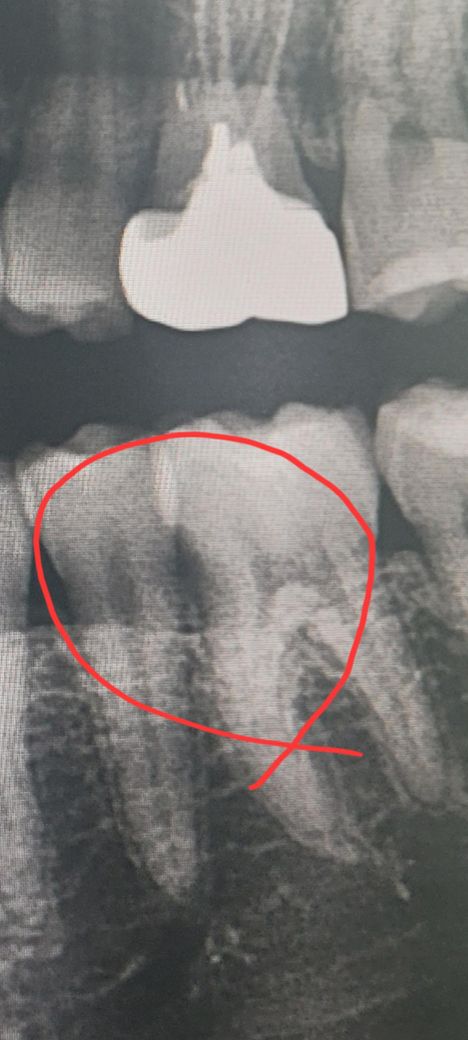

동그라미 부분이 인접면 충치일까요?

동그라미 친 부분이 인접면 충치일까요?

치아 사이가 까맣게 나와서 걱정이 됩니다.

치아가 너무 붙어있어서 저렇게 나온건지 아님 진짜 충치인건지 확인부탁드려요ㅜㅜ

엑스레이상으로 인접면 충치는 아닌거 같습니다. 치아가 겹쳐서 저렇게 보이는거니 걱정하지 않으셔도 될것같습니다 .

해당 부분에 있는 검정색은 충치보다는 방사선사진상 효과로 보이며 충치는 없어 보입니다.

해당부위는 인접면 충치는 아니고 치경부소환으로 인한 왜곡으로 보입니다 인접면 충치를 보고자한다면 교익방사선사진을 찍어보면 좋습니다